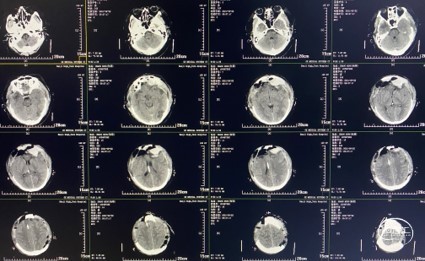

术后复查头颅CT(术后第3天)

患者依旧处于镇静、镇痛状态,但患者颅压持续增高,最高时达22mmHg。

头颅CT:左侧额叶少量渗血,三脑室、双侧侧脑室、环池显露良好。